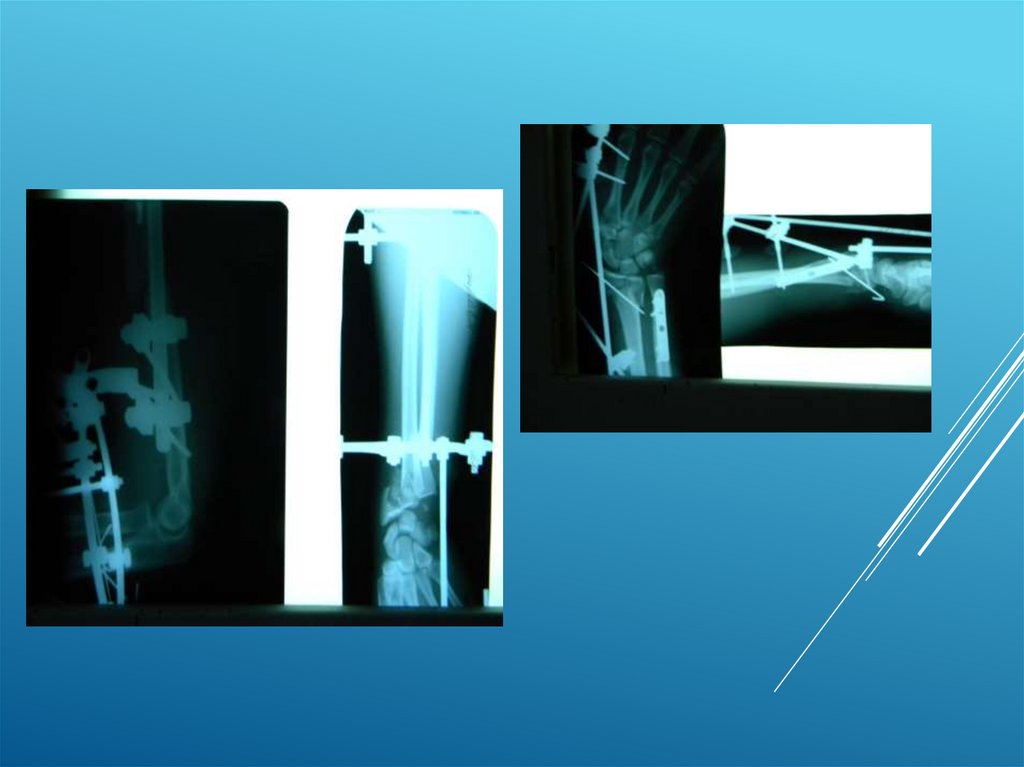

Клинические примеры:

Пациент Д. 32 года

8.

9.

10.

11.

12.

13.

Пациентка К. 54 года

14.

15.

Пациент А. 50 лет